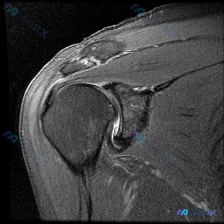

刚看到一个有意思的影像读片病例,整理了分析思路和大家分享一下。 病例基本情况 这是一张提供的单张膝关节矢状位MRI影像,用户核心疑问是:影像中是否存在软骨异常? 影像系统性分析 首先先确认影像基础信息: 1. 序列与定位:这张影像骨髓呈高信号,软组织对比度高,骨皮质为低信号,结构显示清晰,更倾向是T...